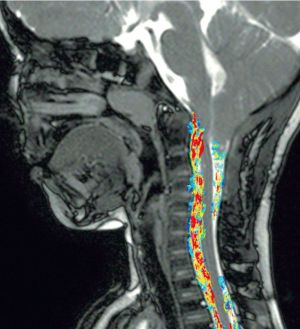

Münster (mfm/tw) – Wenn Zellen durch den Körper ziehen: Mit bildgebenden Verfahren können Mediziner und Wissenschaftler den Weg von Zellen im Körper live verfolgen. Für ihre Arbeit auf diesem Gebiet ist Dr. Rebecca Schmidt, Assistenzärztin im Institut für Klinische Radiologie der Uni Münster, mit einem Nachwuchspreis der Radiologischen Gesellschaft Nordamerikas (RSNA) ausgezeichnet worden: Schmidt entwickelte eine neue spezifische Technik mit, bei der speziell markierte Zellen in die Blutbahn gespritzt und mit Magnetresonanztomographie (MRT) beobachtet werden.

Die MRT ist ein bildgebendes Verfahren, durch das der Körper mittels starker Magnetfelder Schicht für Schicht gescannt werden kann; da Patienten und Probanden für die Untersuchung meist in eine enge Röhre geschoben werden, werden MRT-Geräte umgangssprachlich auch „Röhre“ genannt. Um bestimmte Strukturen im Körper besser sichtbar zu machen, setzen Wissenschaftler und Ärzte Kontrastmittel ein. Diese Mittel werden normalerweise in die Blutbahn injiziert oder über den Mund verabreicht. Bei der Technik, die von Wissenschaftlern der Arbeitsgruppen Experimentelle Magnetresonanztomographie (Leitung: Prof. Dr. Cornelius Faber) und Molekulare Bildgebung (Prof. Dr. Christoph Bremer) entwickelt worden ist, werden die Zellen schon außerhalb des Körpers markiert und dann gespritzt. Anschließend wird durch MRT das Signal des Kontrastmittels erfasst, statt wie in bisher etablierten Techniken das Gewebewassersignal.

Dieses neue Vorgehen erlaubt eine hohe Auflösung mit vergleichsweise einfacher technischer Ausstattung. Wir haben Makrophagen markiert“, erläutert Schmidt – „das sind weiße Blutkörperchen, die als Fresszellen wichtig für die Immunabwehr sind. Im MRT-Gerät können wir beobachten, wie die Makrophagen sich in einer Entzündung verhalten.“Mit bisherigen MRT-Methoden seien solche Einblicke entweder ungenau oder nur mit zusätzlichen Geräten möglich, so Schmidt. „Die neue Methode dagegen kann einfach angewendet werden. Die markierten Zellen senden ein Signal, das im MRT-Gerät sichtbar gemacht wird; durch herkömmliche MRT-Aufnahmen des Körpers können die Signale anschließend anatomisch exakt zugeordnet werden.“